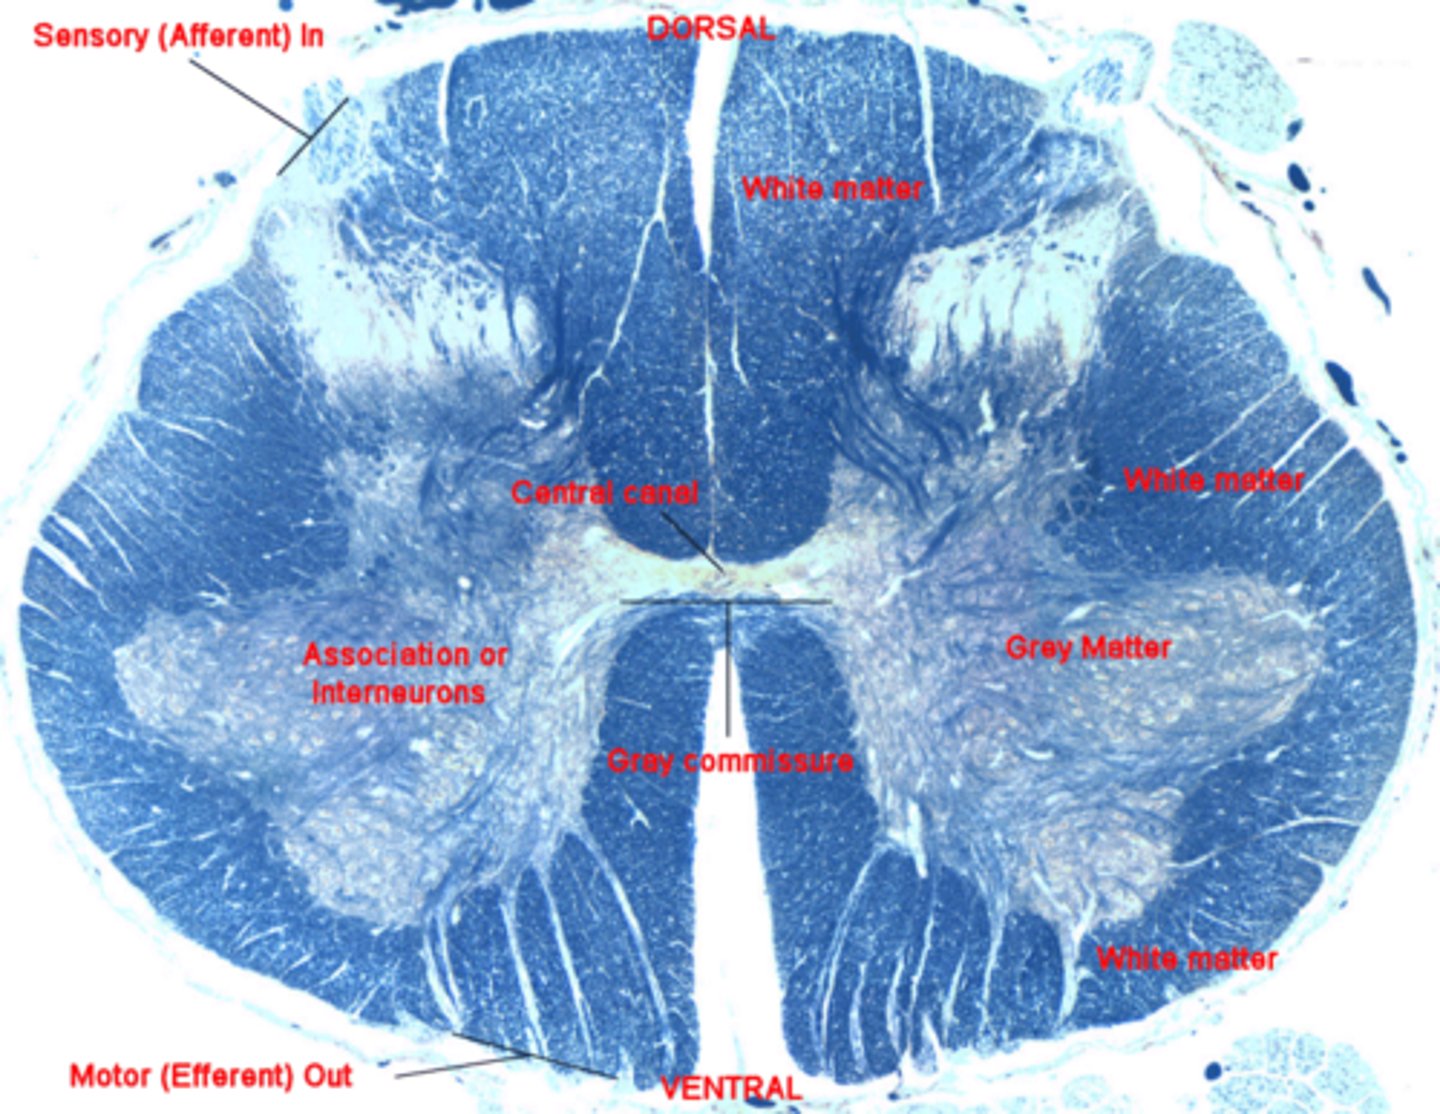

histology of spinal cord

Includes central canal, dorsal horn, ventral horn, site of ventral root, and ventral fissure